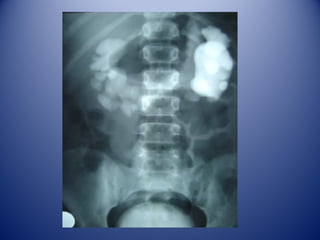

Anterior: ambos riñones con peritoneo y fascia renal.

Rinón Derecho: 1. Cápsula renal. 2. Cara inferior del hígado 3. Ángulo cólico derecho

4. Duodeno 5. Vena cava inferior.

Parte posterior: 11 y 12 costillas.